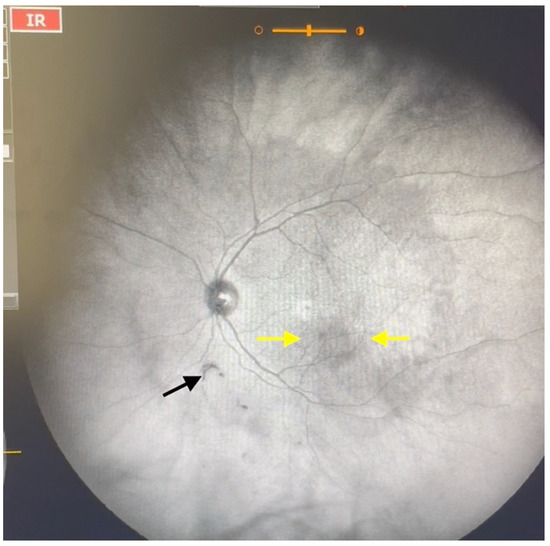

Figure 3.

Ultra-widefield IRcSLO image of an eye with Grade 2 vitreous floaters. Some diffuse shadows are observed within the macular area (yellow arrows). A Weiss ring is also visible outside the macular area (black arrow). See also Video S3.